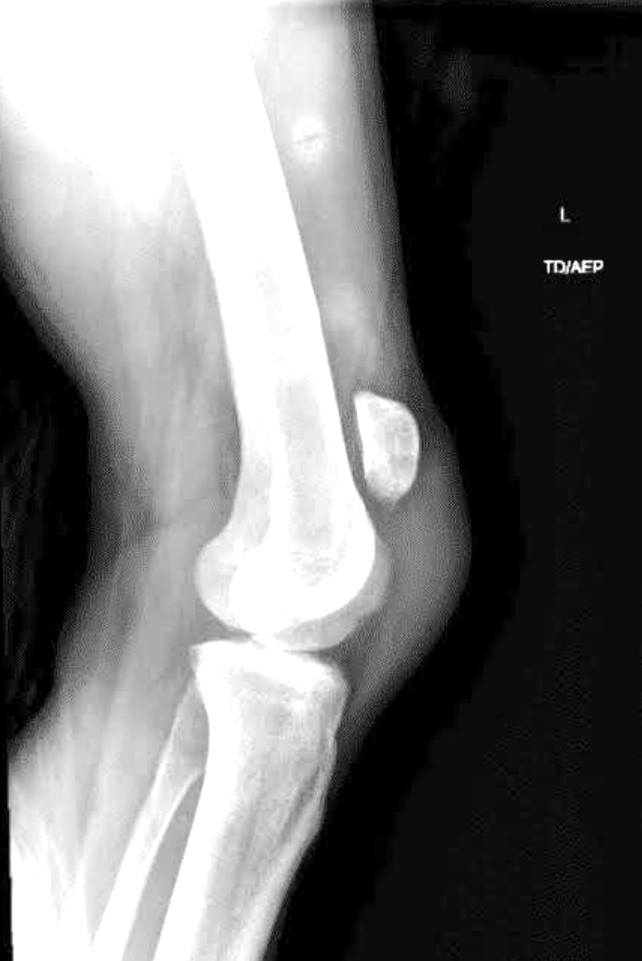

I Felt a Pop and My Elbow Hurts...

A 13-year-old male presents with acute onset of medial elbow pain after throwing a football, at which time he felt a ‘pop’ and is now unable to fully extend at the elbow. He is tender to palpation at the medial epicondyle. He has a history of Little Leaguer’s Elbow.

Bowing out of the Tournament

A 15-year old male presents with right elbow pain and deformity after injury sustained during a wrestling tournament. He has a large joint effusion and prominent olecranon, and is otherwise neurovascularly intact.